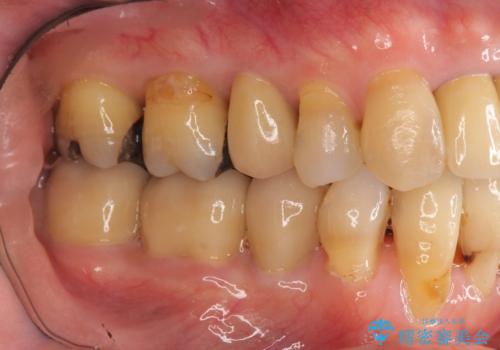

- 前歯の見た目・歯並び・銀歯の見た目の改善を求めて来院されました。

まずガタ付きの強い歯並びをマウスピース矯正インビザラインで整えたのち、セラミック治療による審美性の改善を計画します。

矯正治療が終わったのちに、精度の高いセラミックを装着することでより安定した噛み合わせとなり審美性も兼ね備えた口腔内状態で治療を終了し、今後のメンテナンスを行っていくことができます。